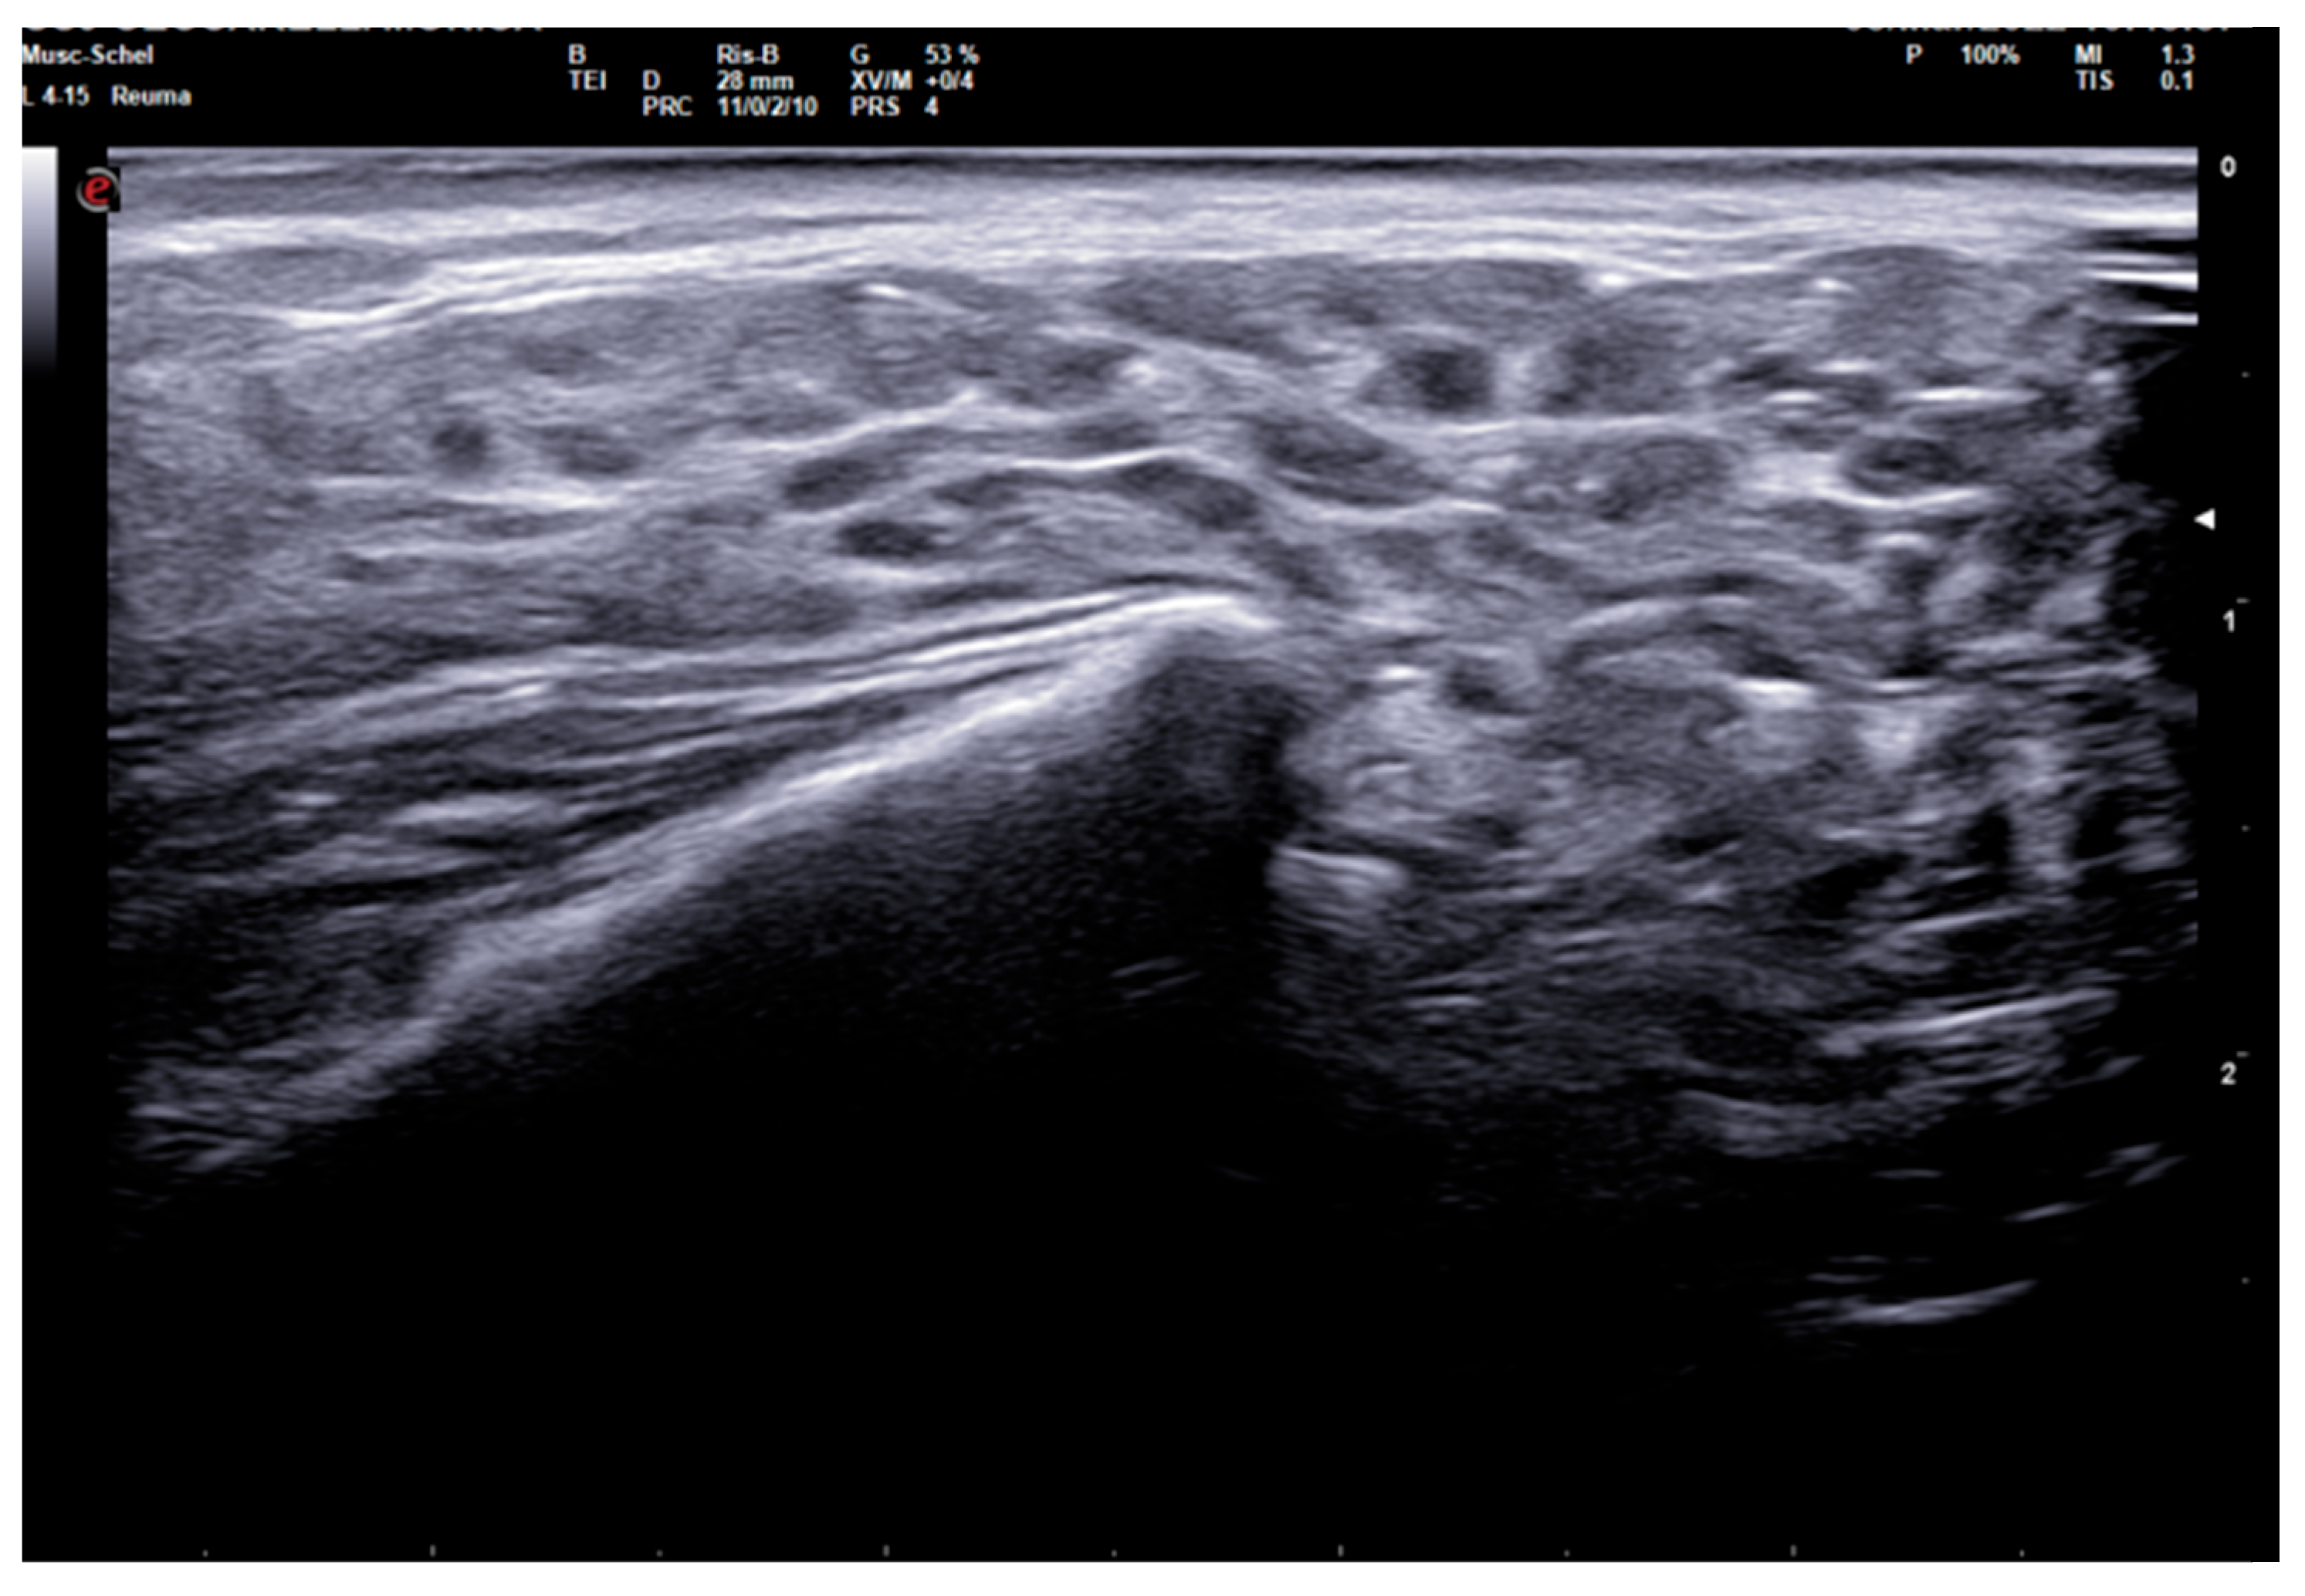

The 0–3-graded OMERACT score was used to assess the ultrasonographic structure of each gland [13,14,15]. The score was applied on each gland, and defined as follows: Grade 0, normal parenchyma (sono-structure comparable to the thyroid gland); Grade 1, mild inhomogeneity without anechoic or hypoechoic areas and hyperechogenic bands; Grade 2, moderate inhomogeneity with focal anechoic or hypoechoic areas; and Grade 3, severe inhomogeneity with diffuse anechoic or hypoechoic areas occupying the entire gland surface [13] (Figure 1).

Figure 1. Parotid SGUS score 3 in primary Sjogren syndrome. Female 51-year-old patient with sicca syndrome, positive Schirmer test, positive autoimmunity (ANA+, Ro-SSA+), positive labial biopsy for SS. A coronal trasverse scan over left parotid (4–15 MHz linear probe) shows diffuse inhomogeneity with hypo-anechoic areas occupying the entire gland volume, surrounded with septal echoic thickening and scanty normal parenchymal tissue (SGUS-OMERACT score = 3).